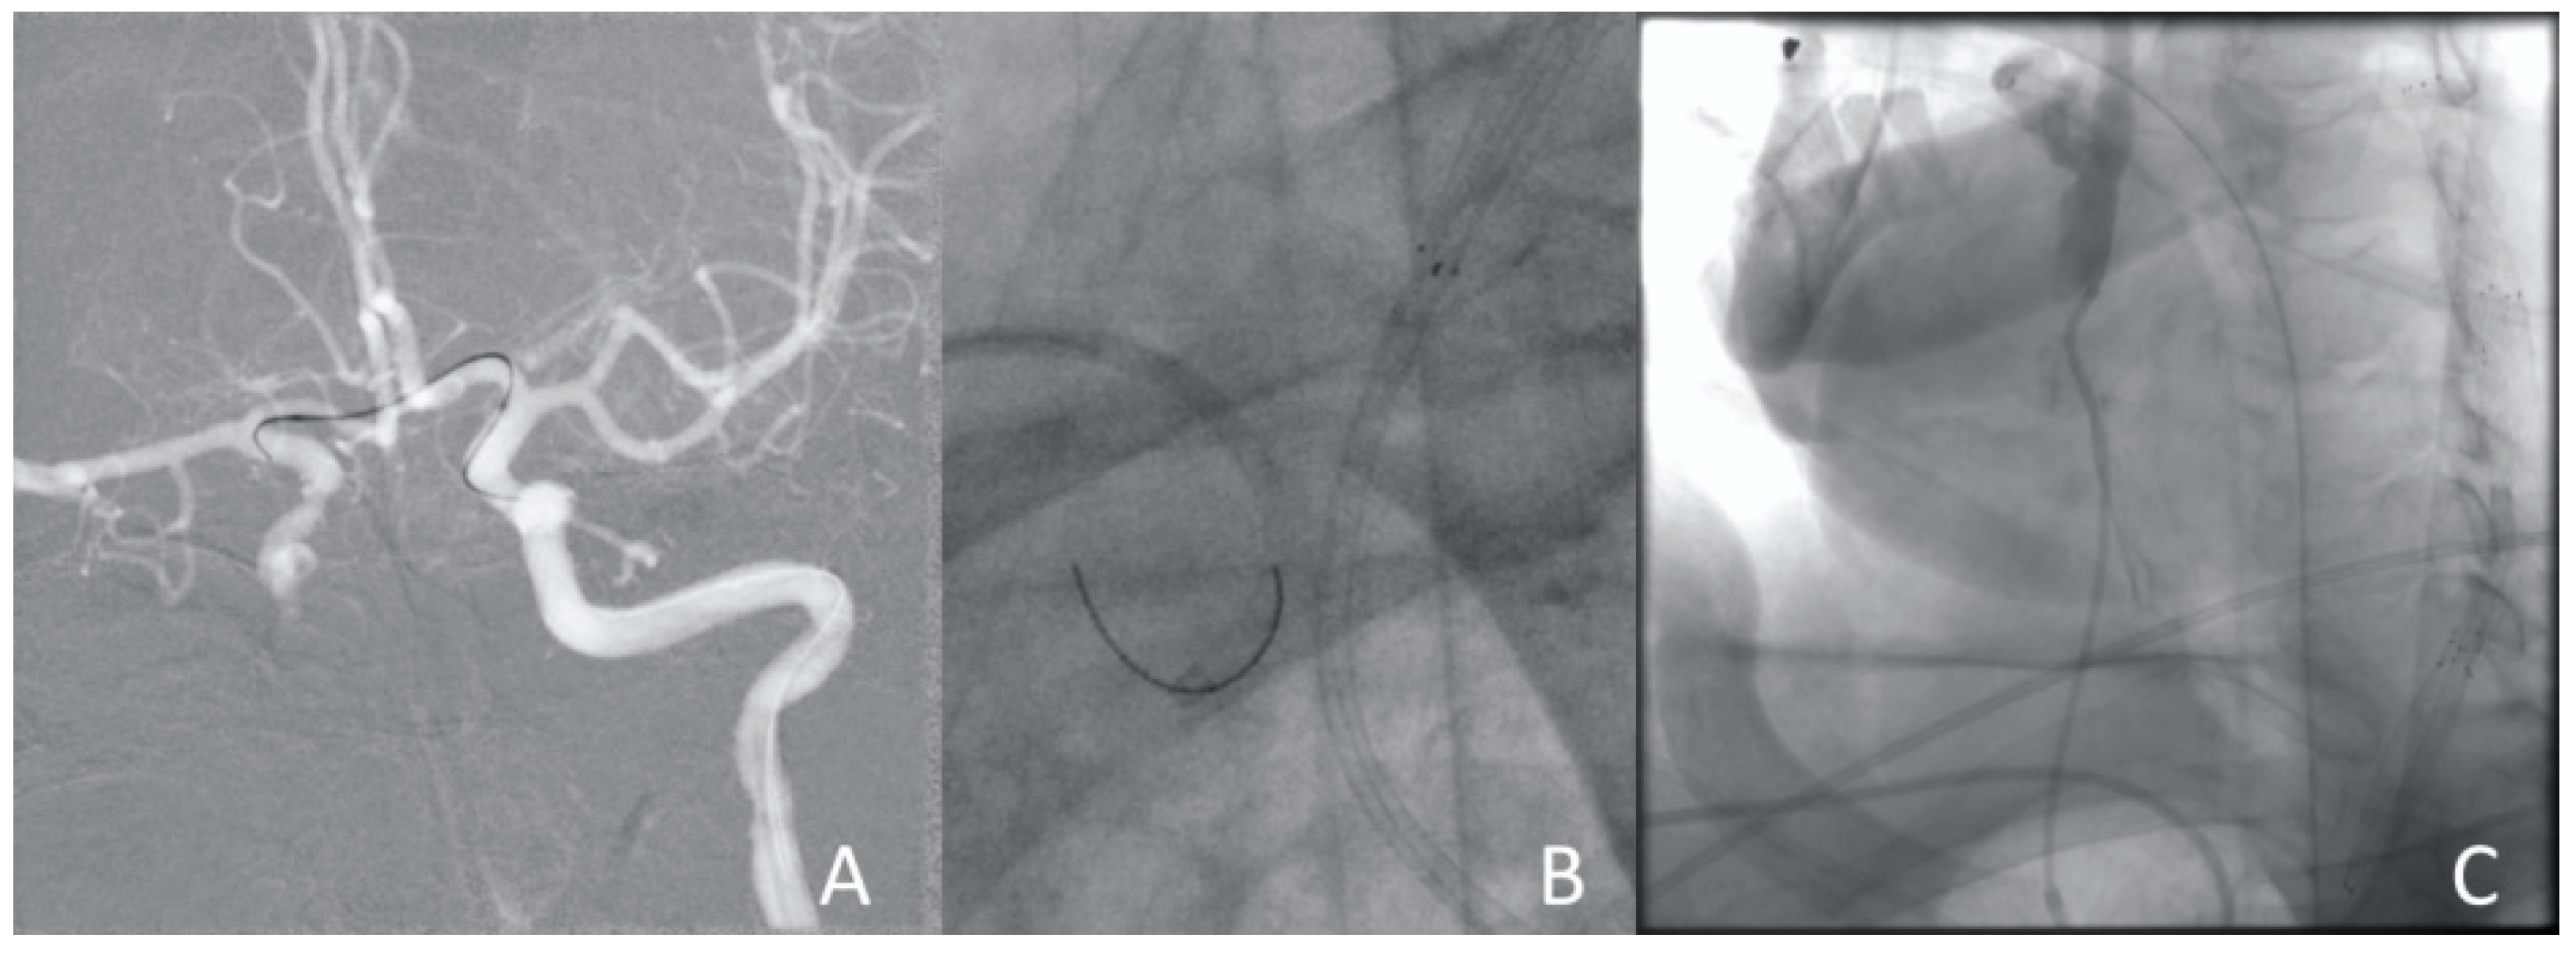

Figure 10.

Clinical Case 2, Patient S., male, 60 years old. Aortic arch angiography. (A) BCT dissection with right CCA and right subclavian artery occlusion; (B) left CCA angiography determines the true lumen compression and a stop of blood flow through the ICA; (C) left subclavian artery angiography determines the stealphenomenon throughout the vertebral arteries.

Considering the surgeon’s experience working with such patients (Clinical Case 1) as well as endovascular team engagement, it was decided to perform emergency endovascular cerebral reperfusion. The patient, without technical difficulties, got a self-expanding stent measuring 6.0 × 150 mm in the left internal and common carotid arteries with protrusion into the aorta; however, control angiography revealed the thrombotic occlusion of the ICA in segment C7. The thromboaspiration using a catheter (6Fr) was performed. Blood flow was restored at the level of TI-CI 2b-3 (Figure 11).

Figure 11.

Clinical Case 2, Patient S., male, 60 years old. Results of the angiography: (A) left ICA occlusion from the bifurcation, the external carotid artery is passable; (B) left ICA stenting with the stent protrusion into the aorta; (C) stagnation of contrast in ICA due to a thrombus in the C1 segment of the ICA; (D) restoration of blood flow through the cerebral arteries.